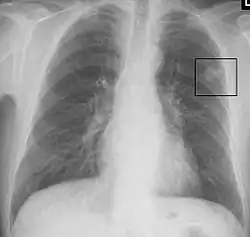

Wenn Tumoren wachsen, können sie das gesunde Nachbargewebe verdrängen, ohne es zu zerstören, oder aber zerstörend in das Nachbargewebe einwachsen (invasiv-destruierendes Wachstum). Beide Formen des Wachstums können zu lokalen Komplikationen führen. So kann beispielsweise durch expansives Wachstum ein blutführendes Gefäß komprimiert werden. Die in der Folge auftretende Durchblutungsstörung des abhängigen Gewebes kann dazu führen, dass dieses Gewebe abstirbt (Nekrose). Infiltrierend-destruierendes Wachstum kann beispielsweise in Hohlorganen wie dem Darm durch Zerstörung des Gewebes zu Durchbrüchen (Perforationen) und Fistelungen führen. Tumorfisteln führen häufig durch Infektionen zu weiteren Komplikationen.[58] Bei Lungenkrebs, Brustkrebs und anderen Tumoren im Brustkorb kann es durch ein Exsudat zu einem Pleuraerguss kommen.[59]

Tumoren können auf unterschiedliche Weise den gesamten Organismus beeinflussen. Vom Primärtumor ausgehende Tochtergeschwulste können sich in anderen Organen ansiedeln und hier durch lokales Wachstum Gewebe zerstören und zu Funktionsstörungen führen. Bei vielen Patienten kommt es im Laufe der Krebserkrankung zu einem allgemeinen Kräfteverfall und Gewichtsverlust (Tumorkachexie, Auszehrung). Zu den systemischen Wirkungen von Tumoren werden auch sogenannte paraneoplastische Syndrome gerechnet. Hierbei kommt es zu charakteristischen Symptomen in verschiedenen Organsystemen, die letztlich durch den Tumor verursacht werden. Beispielsweise kann ein Lungenkrebs zu einer Störung der hormonellen Regulation des Wasserhaushalts führen (Schwartz-Bartter-Syndrom).[58]